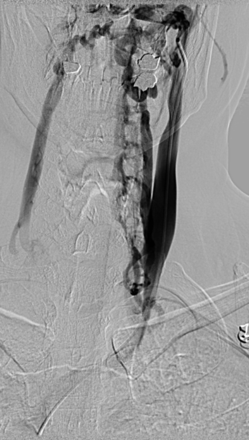

Stenosis or malformations of the AV were observed in 9 subjects (Fig 1). Those of the right IJV were found in 19 subjects (Fig 2), stenosis or malformations of the left IJV in 17 subjects (Fig 3), and those of the ILP in 15 subjects (Fig 4).

Selective catheterization of the azygos vein in a 37-year-old patient with secondary-progressive MS in which the injection of contrast medium showed the presence of a twisting of the AV associated with a shunt with the hemiazygous venous system. Note the opacification of the intraspinal venous plexus.

Selective catheterization of the left and right internal jugular veins in a 35-year-old patient with relapsing-remitting MS. Venous stenosis at the level of the section J2 of the right IJV and of its origin is shown, with associated drainage in spinal venous plexus through a collateral branch. The left IJV does not present alterations in size and drainage.

Selective catheterization of the left internal jugular vein in a 41-year-old patient with primary-progressive MS. After injection of contrast medium, stenosis of segment J1 with reflux in both vertebral veins and opacification of the vertebral venous plexus is documented.